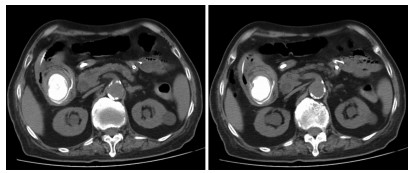

Clinical effect of simultaneous surgical resection of hepatic and pancreatic lesions versus systemic chemotherapy in treatment of resectable pancreatic cancer with liver metastasis

2022, 38(3): 622-628. DOI: 10.3969/j.issn.1001-5256.2022.03.023

Abstract(1384) HTML (1170) PDF (2734KB)(54)

Abstract:

Objective  To investigate the clinical effect of simultaneous surgical resection of hepatic and pancreatic lesions versus systemic chemotherapy in treatment of resectable pancreatic cancer with liver metastasis (PCLM).  Methods  A retrospective analysis was performed for related data of the patients with PCLM who were admitted to Shengjing Hospital of China Medical University from January 2013 to May 2020, and the patients with resectable PCLM were screened out and then divided into surgery group and chemotherapy group. The propensity score matching (PSM) method was used to reduce the impact of data bias and confounding factors. The independent samples t-test or the Mann- Whitney U test was used for comparison of continuous data between two groups, and the chi-square test was used for comparison of categorical data between two groups. The Kaplan-Meier method was used to calculate survival time, and the log-rank test was used for evaluation. The univariate and multivariate Cox regression models were used to investigate the independent risk factors for survival.  Results  A total of 56 patients with resectable PCLM were screened out, with 33 patients in the surgery group and 23 patients in the chemotherapy group, and there were 15 patients in each group after PSM. The surgery group had a significantly shorter median overall survival time than the chemotherapy group before PSM (6.6 months vs 10.4 months, χ2=4.476, P=0.034) and after PSM (6.4 months vs 10.5 months, χ2=4.309, P=0.038). The multivariate Cox regression analysis showed that poorly differentiated tumor (hazard ratio [HR]=4.945, 95% confidence interval [CI]: 1.980-12.348, P=0.001) and absence of postoperative chemotherapy (HR=3.670, 95%CI: 1.437-9.376, P=0.007) were independent risk factors for poor prognosis in patients with PCLM.  Conclusion  Compared with chemotherapy, simultaneous surgical resection of hepatic and pancreatic lesions fails to prolong the overall survival time of patients with resectable PCLM. Patients with poorly differentiated tumor and those without postoperative chemotherapy tend to have poor prognosis.